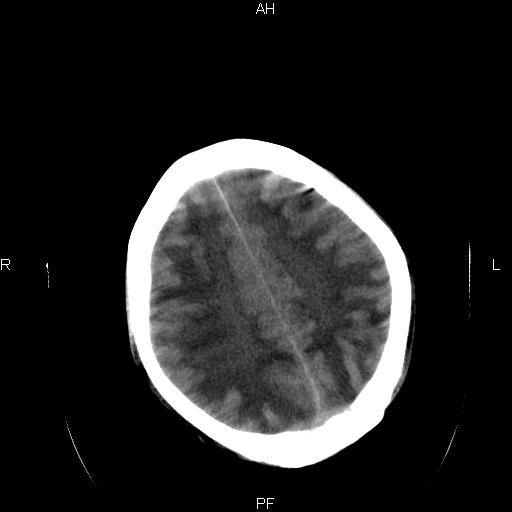

男性,45岁,缄默少语,四肢无力一个月。骨窗未见明确异常。

弥漫性脑白质低密度症

对称性脑白质广泛低密度。有高血压史及大量饮酒史吗?

考虑重度脑白质稀疏症。

弥漫性脱髓鞘病变,建议mri检查。

双侧弥漫性对称性全累及性(外囊亦有累及)脑白质病

患者病程月余,脑沟裂闭合,第三脑室较窄,提示应该有较明显的脑白质水肿,考虑有持续性炎性病变

综合考虑脑白质感染性或非感染性炎症可能性大,不排除为克雅氏病